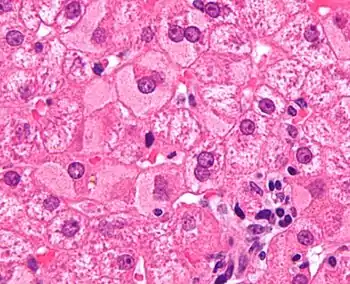

| Micrograph showing ground glass hepatocytes, which are seen in chronic hepatitis B infections (a type of viral hepatitis), and represent accumulations of viral antigen in the endoplasmic reticulum. H&E stain. | |